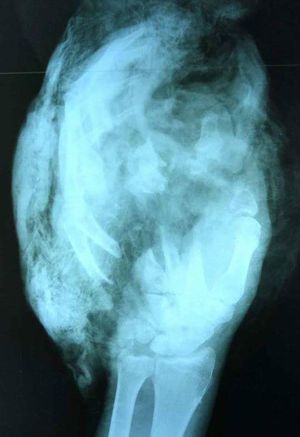

A cut down hand

This hand was cut by a circular sheet (woodcutter). The men arrived with the ambulance at the hospital and his hand could't be saved.